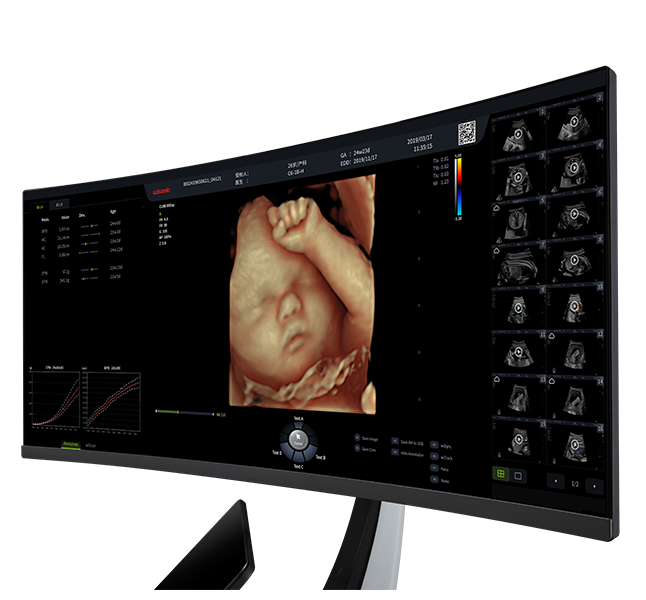

Système Intelligent d'échographie de Dépistage Obstétrical

Plateforme CS de pointe dotée d'une technologie d'imagerie super-résolution unique dans l'industrie

Conceptions ergonomiques et flux de travail d'IA efficace, offrant une expérience utilisateur extraordinaire